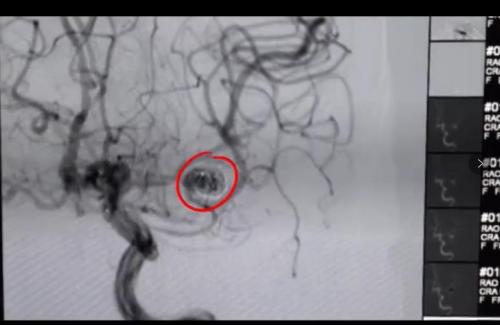

(患者术前脑动脉瘤血管造影)

(手术中血管造影)

据李宏宇主任介绍,李阿姨脑动脉瘤大小8mmX6mm,在他多年临床工作中也属罕见。在术前准备后中午12时30分手术正式开始,通俗讲动脉瘤介入栓塞治疗就是将介入导丝填充进血管瘤内,让血液不再经过血管瘤,从而让这个大脑内部的“*弹炸**”不会因血压“引爆”。在李宏宇手术团队的配合下,介入导丝从患者的腿部动脉一点一点推入到患者脑内的血管瘤病灶处,紧接着在血管瘤内填入导丝封住血管瘤。经过2个多小时紧张工作,手术顺利完成。